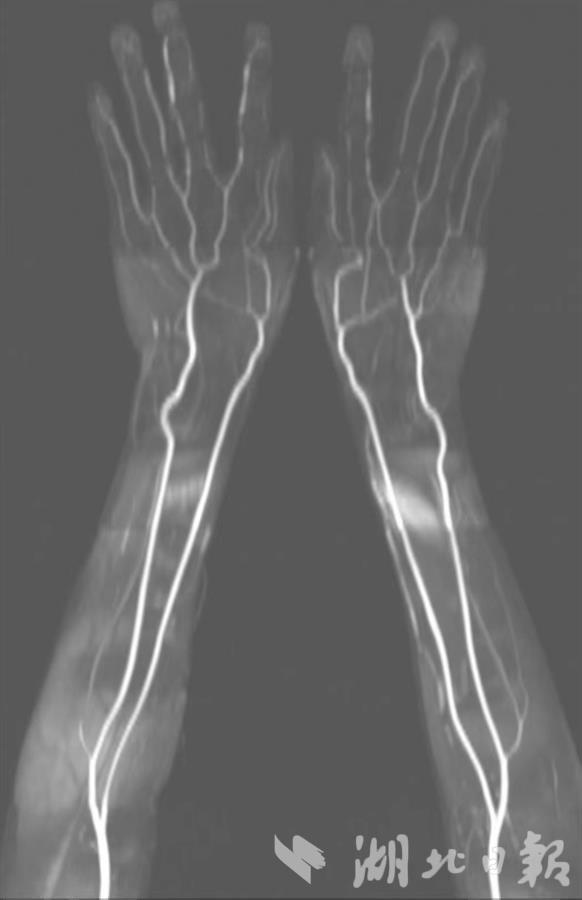

为此,吴刚团队多年来专注于磁共振新技术新序列的开发与改良。经过多年努力,他们研发出一种无需电离辐射、无需造影剂、可在短时间内反复多次扫描的磁共振动脉造影(MRA)技术,解决了全身血管诊断难题。目前,此技术已经成熟应用于临床。

吴刚介绍,新技术不仅能获得患者胸部大动脉的优质影像,也能清晰显示双足、双手小动脉影像,还能用于显示肾功能不全患者的肾动脉、糖尿病血管病、动脉粥样硬化等。其动脉成像图像质量高,零射线,零造影剂,对身体危害小。他提醒,一旦发现皮肤红斑、口干、眼干等症状要警惕血管炎,需及时到正规医院找专科医生进行检查,以免延误治疗。